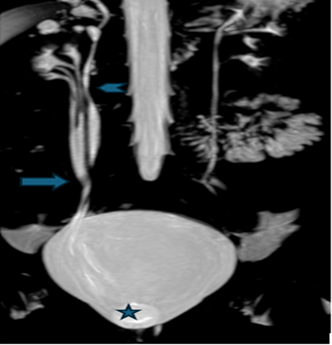

Figure 1: MR Urography coronal MIP Image

shows right kidney with triplex collecting system, The lower two moieties on

the right show fusion of the ureters at the L4 vertebral level (

) draining normally into the right

vesico-ureteric junction, terminating into a ureterocele (

). The upper moiety ureter is marked by

Figure 2 (a,b,c): MR Urography image